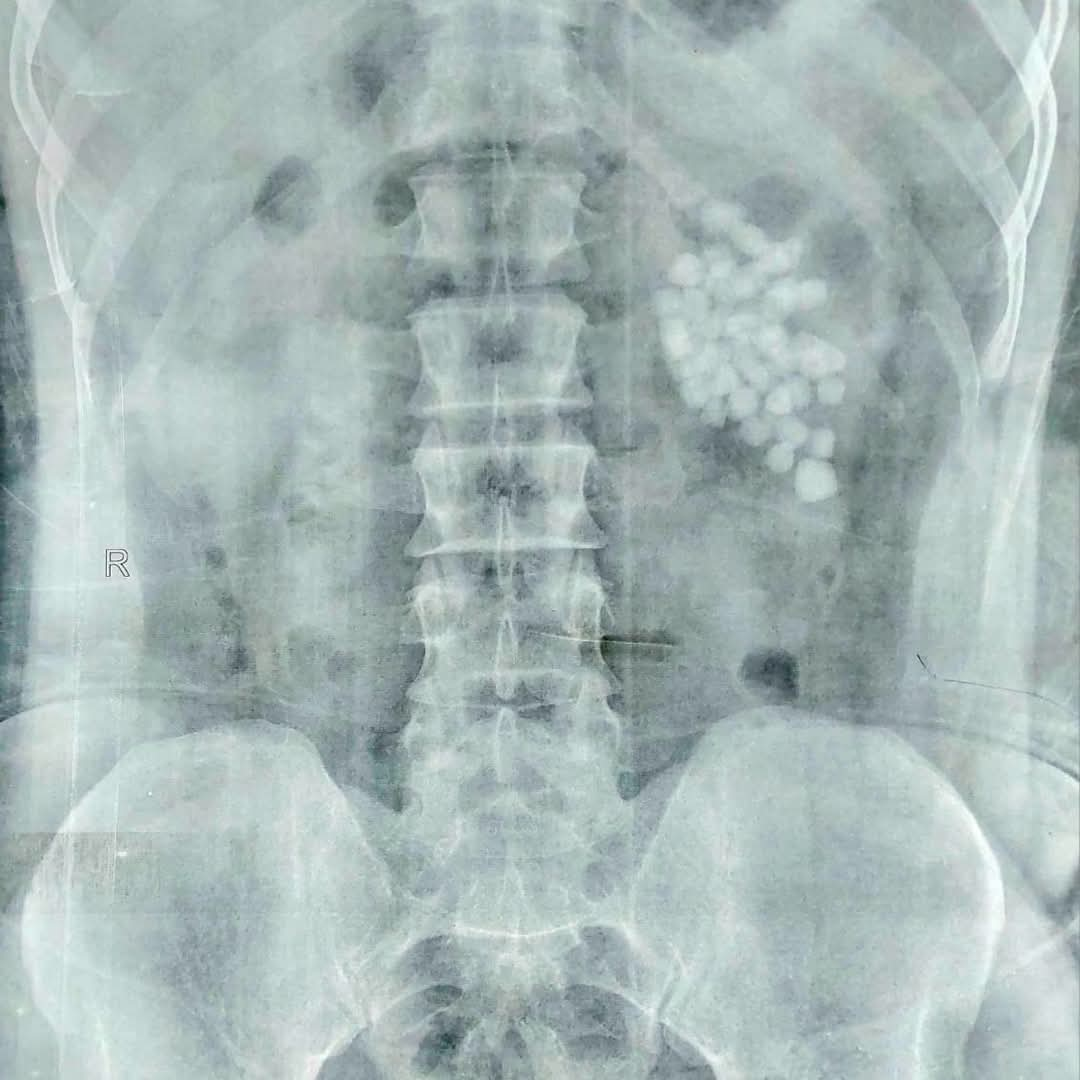

وأوضح دكتور مصطفى عبد الرازق رئيس قسم المسالك البولية أن المريض وصل إلى المستشفى وهو يعاني من آلام متكررة وارتفاع في نسبة الأملاح، وبعد إجراء الفحوصات اللازمة تبيّن وجود عدد كبير من الحصوات المتجمعة في حوض الكلية اليسرى، مما استدعى التدخل الجراحي الفوري للحفاظ على سلامة الكلية.

وتم تجهيز المريض للعملية وإجراء التخدير العام، ثم بدأ الفريق الطبي العمل بتقنية منظار الكلية عن طريق الجلد، وهي من أحدث الأساليب التي تسمح بإزالة الحصوات الكبيرة والمتعددة بدون فتح جراحي. وتم عمل فتحة جراحية صغيرة لا تتجاوز سنتيمترًا واحدًا للوصول إلى الكلية، ثم تفتيت الحصوات باستخدام تقنيات التفتيت الهوائي والليزر تبعًا لطبيعة كل حصوة.

استغرقت العملية نحو ساعتين، تمكن خلالها الفريق الطبي من استخراج الحصوات كاملة مع التأكد من تنظيف حوض الكلية تمامًا لمنع تكرار المشكلة مستقبلًا، كما تم وضع أنبوب تصريف مؤقت لضمان خروج السوائل بشكل آمن بعد العملية. وخرج المريض من غرفة العمليات في حالة مستقرة، بينما تمت متابعة علاماته الحيوية داخل الإفاقة، وسط تحسن ملحوظ في حالته العامة ووظائف الكلى.